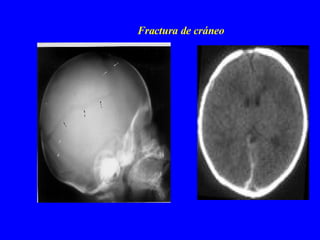

Fractura de cráneo